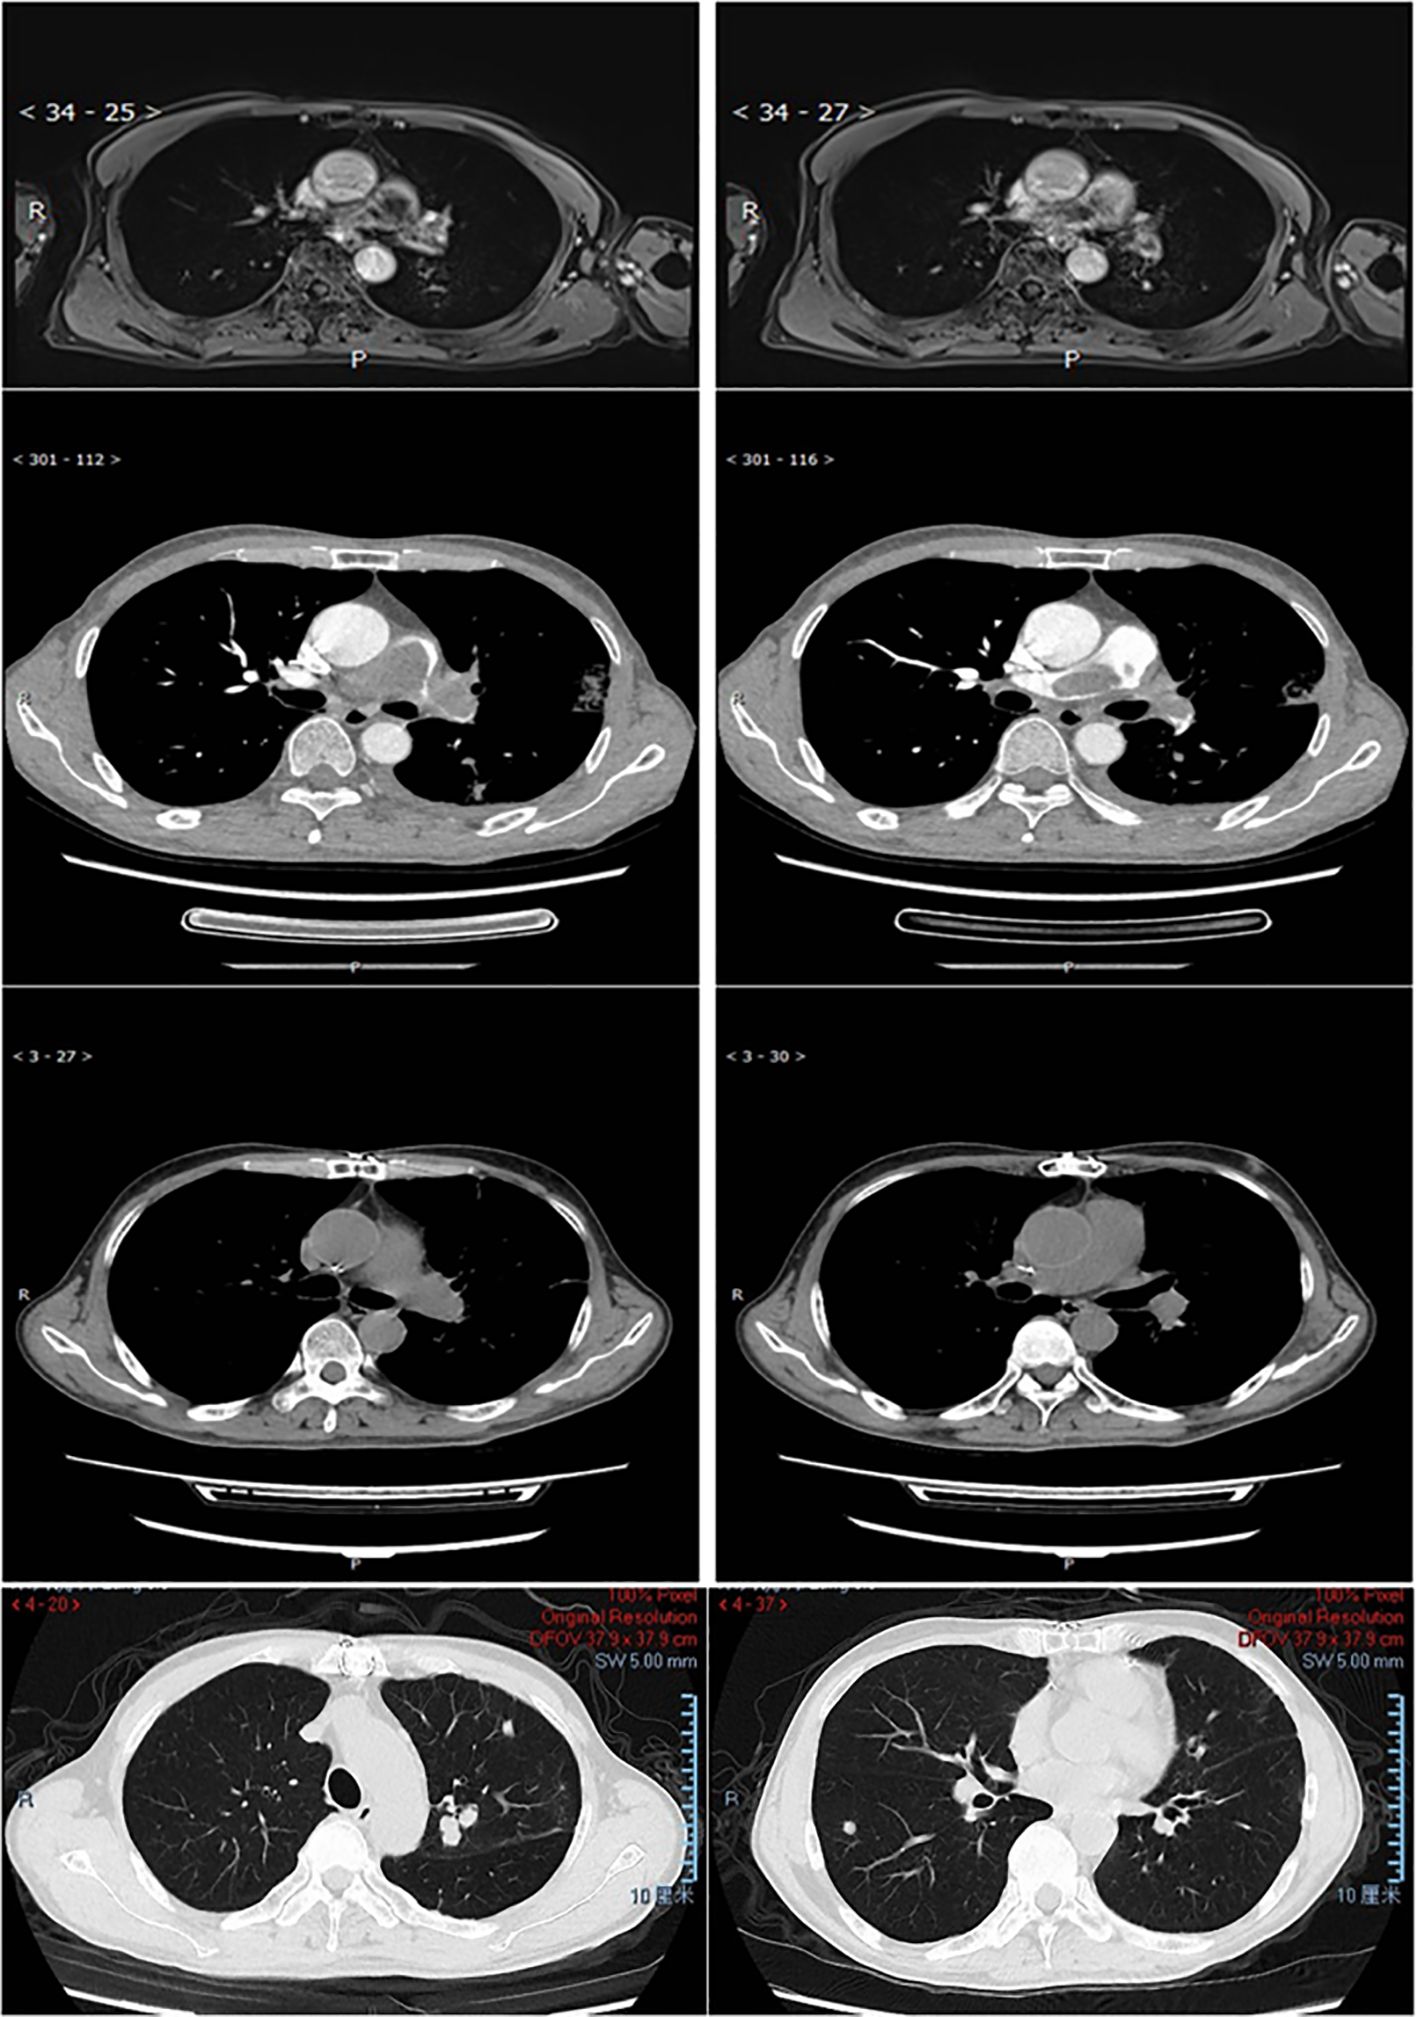

Three patients received immune checkpoint inhibitor (ICI) therapy during their disease course. Patient P001, an adult patient with pulmonary artery intimal sarcoma involving the pulmonary trunk (PT), left pulmonary artery (LPA), and right pulmonary artery (RPA), received adjuvant sintilimab following pulmonary endarterectomy (PEA) and has remained progression-free for over 14 months to date. The tumor exhibited 15% PD-L1 expression and strong MDM2 positivity, with an MDM2 copy number gain (CNG) of 9.15. Patient P007, an adult patient also diagnosed with pulmonary artery intimal sarcoma involving the PT, LPA, and RPA, experienced tumor recurrence 12 months post-PEA. This patient subsequently underwent 4 cycles of combined therapy including chemotherapy, the antiangiogenic agent anlotinib, and sintilimab, followed by sintilimab maintenance therapy, achieving sustained tumor control for over 56 months since initial diagnosis (Figure 4). Patient P005, an adult patient with pulmonary artery intimal sarcoma confined to the LPA, underwent wedge resection of the left lower lobe. Despite negative PD-L1 expression, adjuvant therapy comprising combined chemotherapy, antiangiogenic therapy, and an ICI was administered; however, the patient died 11 months post-surgery. The tumor was MDM2-positive, with an MDM2 CNG of 5.37.

Figure 4

Lung MRI/CT scan of patient P007. Rows 1 (MRI) and 2 (CTA) show pulmonary artery intimal sarcoma involving PT, LPA, and RPA at diagnosis. Rows 3-4, 12 months post-PEA, demonstrate relapse with tumor in left upper lobe, right lower lobe, and peripheral lung nodules.

Figure 4. MRI/CT scan of the lung in patient P007. Row 1 (MRI) 2 (CTA), pulmonary artery intimal sarcoma involved PT, LPA, and RPA at diagnosis. Row 3-4, 12 months after PEA the patient relapsed with tumor involved left upper lobe, right lower lobe, and multiple little nodules in the peripheral lung.